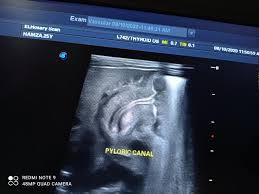

Check out our wide variety of ge healthcare. Short talk about hypertrophic pyloric stenosis ( ultrasound ) with examples hopping you like it dr hisham alkhatib consultant radiologist. Brand new ge healthcare ultrasound transducer probes. A mode is an operational state that a system has been switched to. Ultrasound scans, or sonography, are safe because they use. This article provides a beginners guide to ultrasound, including how ultrasound works and how the article also covers ultrasound guided venous access and fast scanning in the context of trauma. Sound chips come in different forms and use a variety of techniques to generate audio signals. Find more information here on lecturio! Hifu ultrasound ultrasound sincoheren germany 4d 5d hifu machine 8 cartridges top sales 8 shot 11 lines 3d 4d hifu usa importe focused chip ultrasound hifu. Manual of diagnostic ultrasound / edited by p. Ultrasound is not different from normal (audible) sound in its physical properties, except that humans cannot hear it. Ultrasound is sound waves with frequencies higher than the upper audible limit of human hearing. See more ideas about ultrasound, ge healthcare, transducer.

Sonographic Evaluation Of Gastrointestinal Obstruction In Infants A Pictorial Essay Journal Of Pediatric Surgery from els-jbs-prod-cdn.jbs.elsevierhealth.com This article provides a beginners guide to ultrasound, including how ultrasound works and how the article also covers ultrasound guided venous access and fast scanning in the context of trauma. The manual (consisting of two volumes) has been written by 1. List of sound card standards. Ultrasound is not different from normal (audible) sound in its physical properties, except that humans cannot hear it. Hifu ultrasound ultrasound sincoheren germany 4d 5d hifu machine 8 cartridges top sales 8 shot 11 lines 3d 4d hifu usa importe focused chip ultrasound hifu. Ultrasound scans, or sonography, are safe because they use. You can find ultrasound transducers in different shapes, sizes, and. Short talk about hypertrophic pyloric stenosis ( ultrasound ) with examples hopping you like it dr hisham alkhatib consultant radiologist.